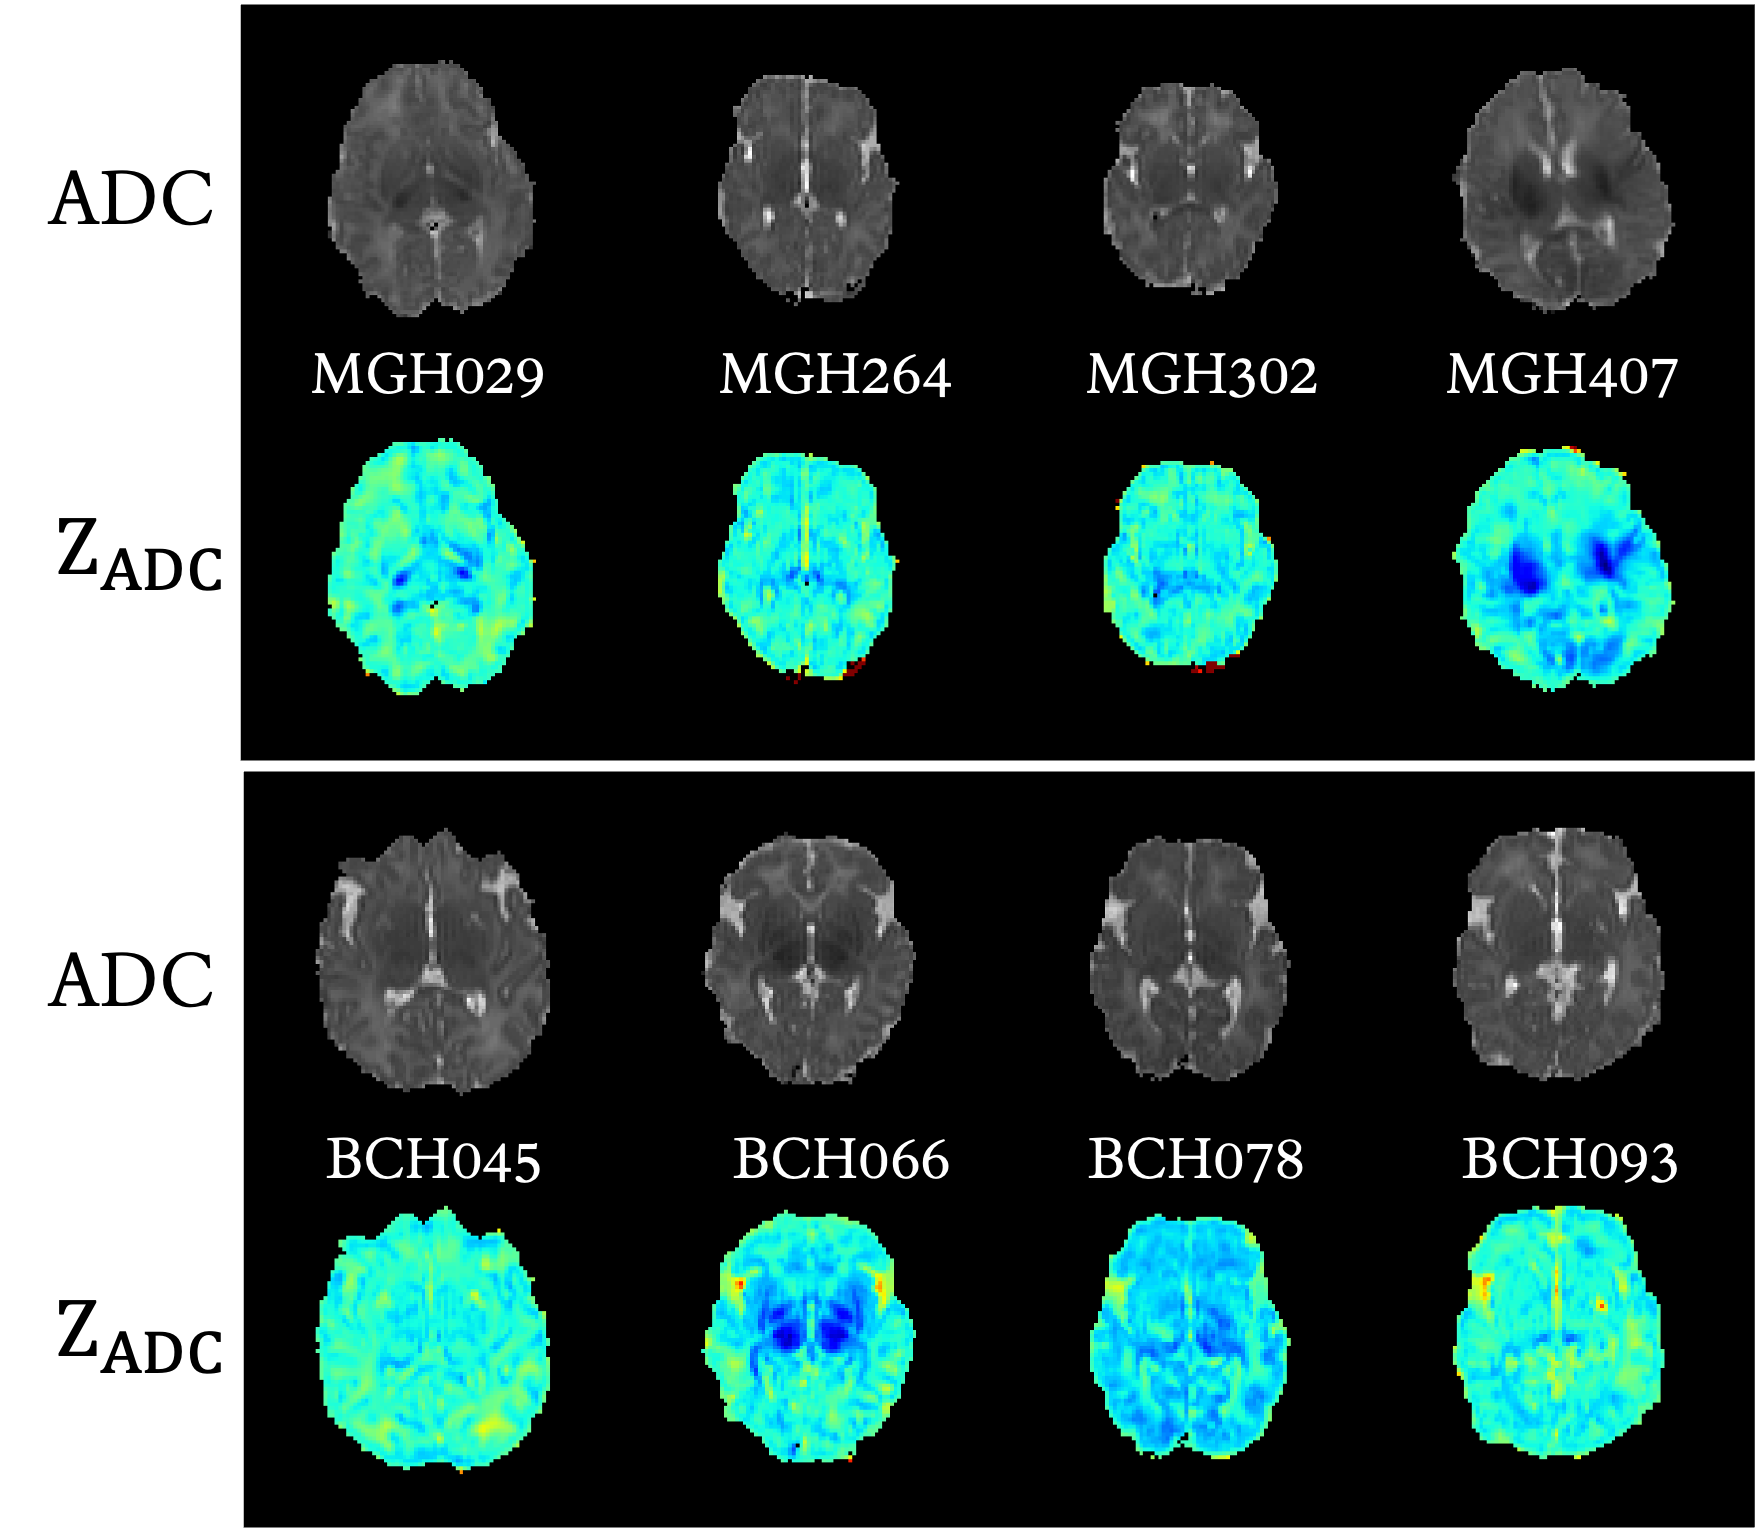

Figure 1: Representative cases for 4 HIE patients from MGH and BCH. For each patient, in the upper panel: apparent diffusion coefficient (ADC) maps; in the bottom panel: ZADCsubscript𝑍𝐴𝐷𝐶Z_{ADC} maps.

We provide ADC and ZADCsubscript𝑍𝐴𝐷𝐶Z_{ADC} for HIE outcome predictions, such information has been verified crucial for HIE outcome predictions. Figure 1 shows the ADC map, ZADCsubscript𝑍𝐴𝐷𝐶Z_{ADC} map from MGH and BCH. For details of ADC and ZADCsubscript𝑍𝐴𝐷𝐶Z_{ADC}, please refer our Part.I paper (Bao et al., 2023).